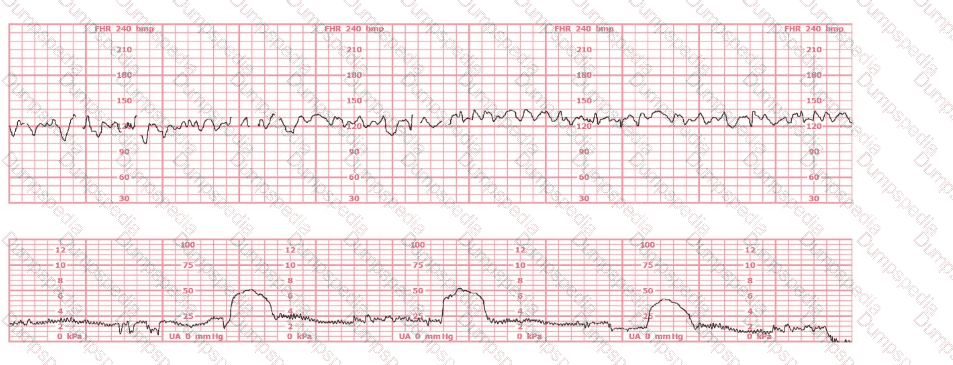

A nulliparous woman at term presents with leaking fluid. Rupture of membranes confirmed. After 6 hours she is completely dilated, +2 station, has been pushing 2 hours with oxytocin at 10 mU/min. The fetal tracing is shown. What is the next step in management?